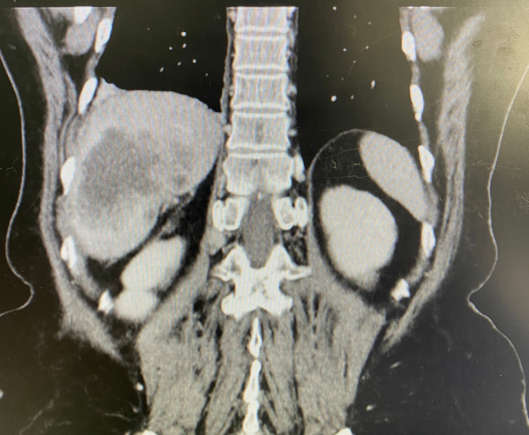

O colangiocarcinoma, também conhecido como câncer biliar, é uma doença rara na qual células malignas (cancerígenas) se formam nos canais biliares.

Os canais biliares são uma série de tubos finos que transportam um fluido chamado bile do fígado para a vesícula biliar e para o intestino delgado, como forma de ajudar a digerir as gorduras dos alimentos.

O câncer biliar pode ser encontrado em qualquer lugar no sistema de canais biliares. Com base em onde os cânceres começam, eles são agrupados em três tipos: câncer de via biliar intra-hepático; câncer de via biliar perihilar; e câncer de via biliar distal.